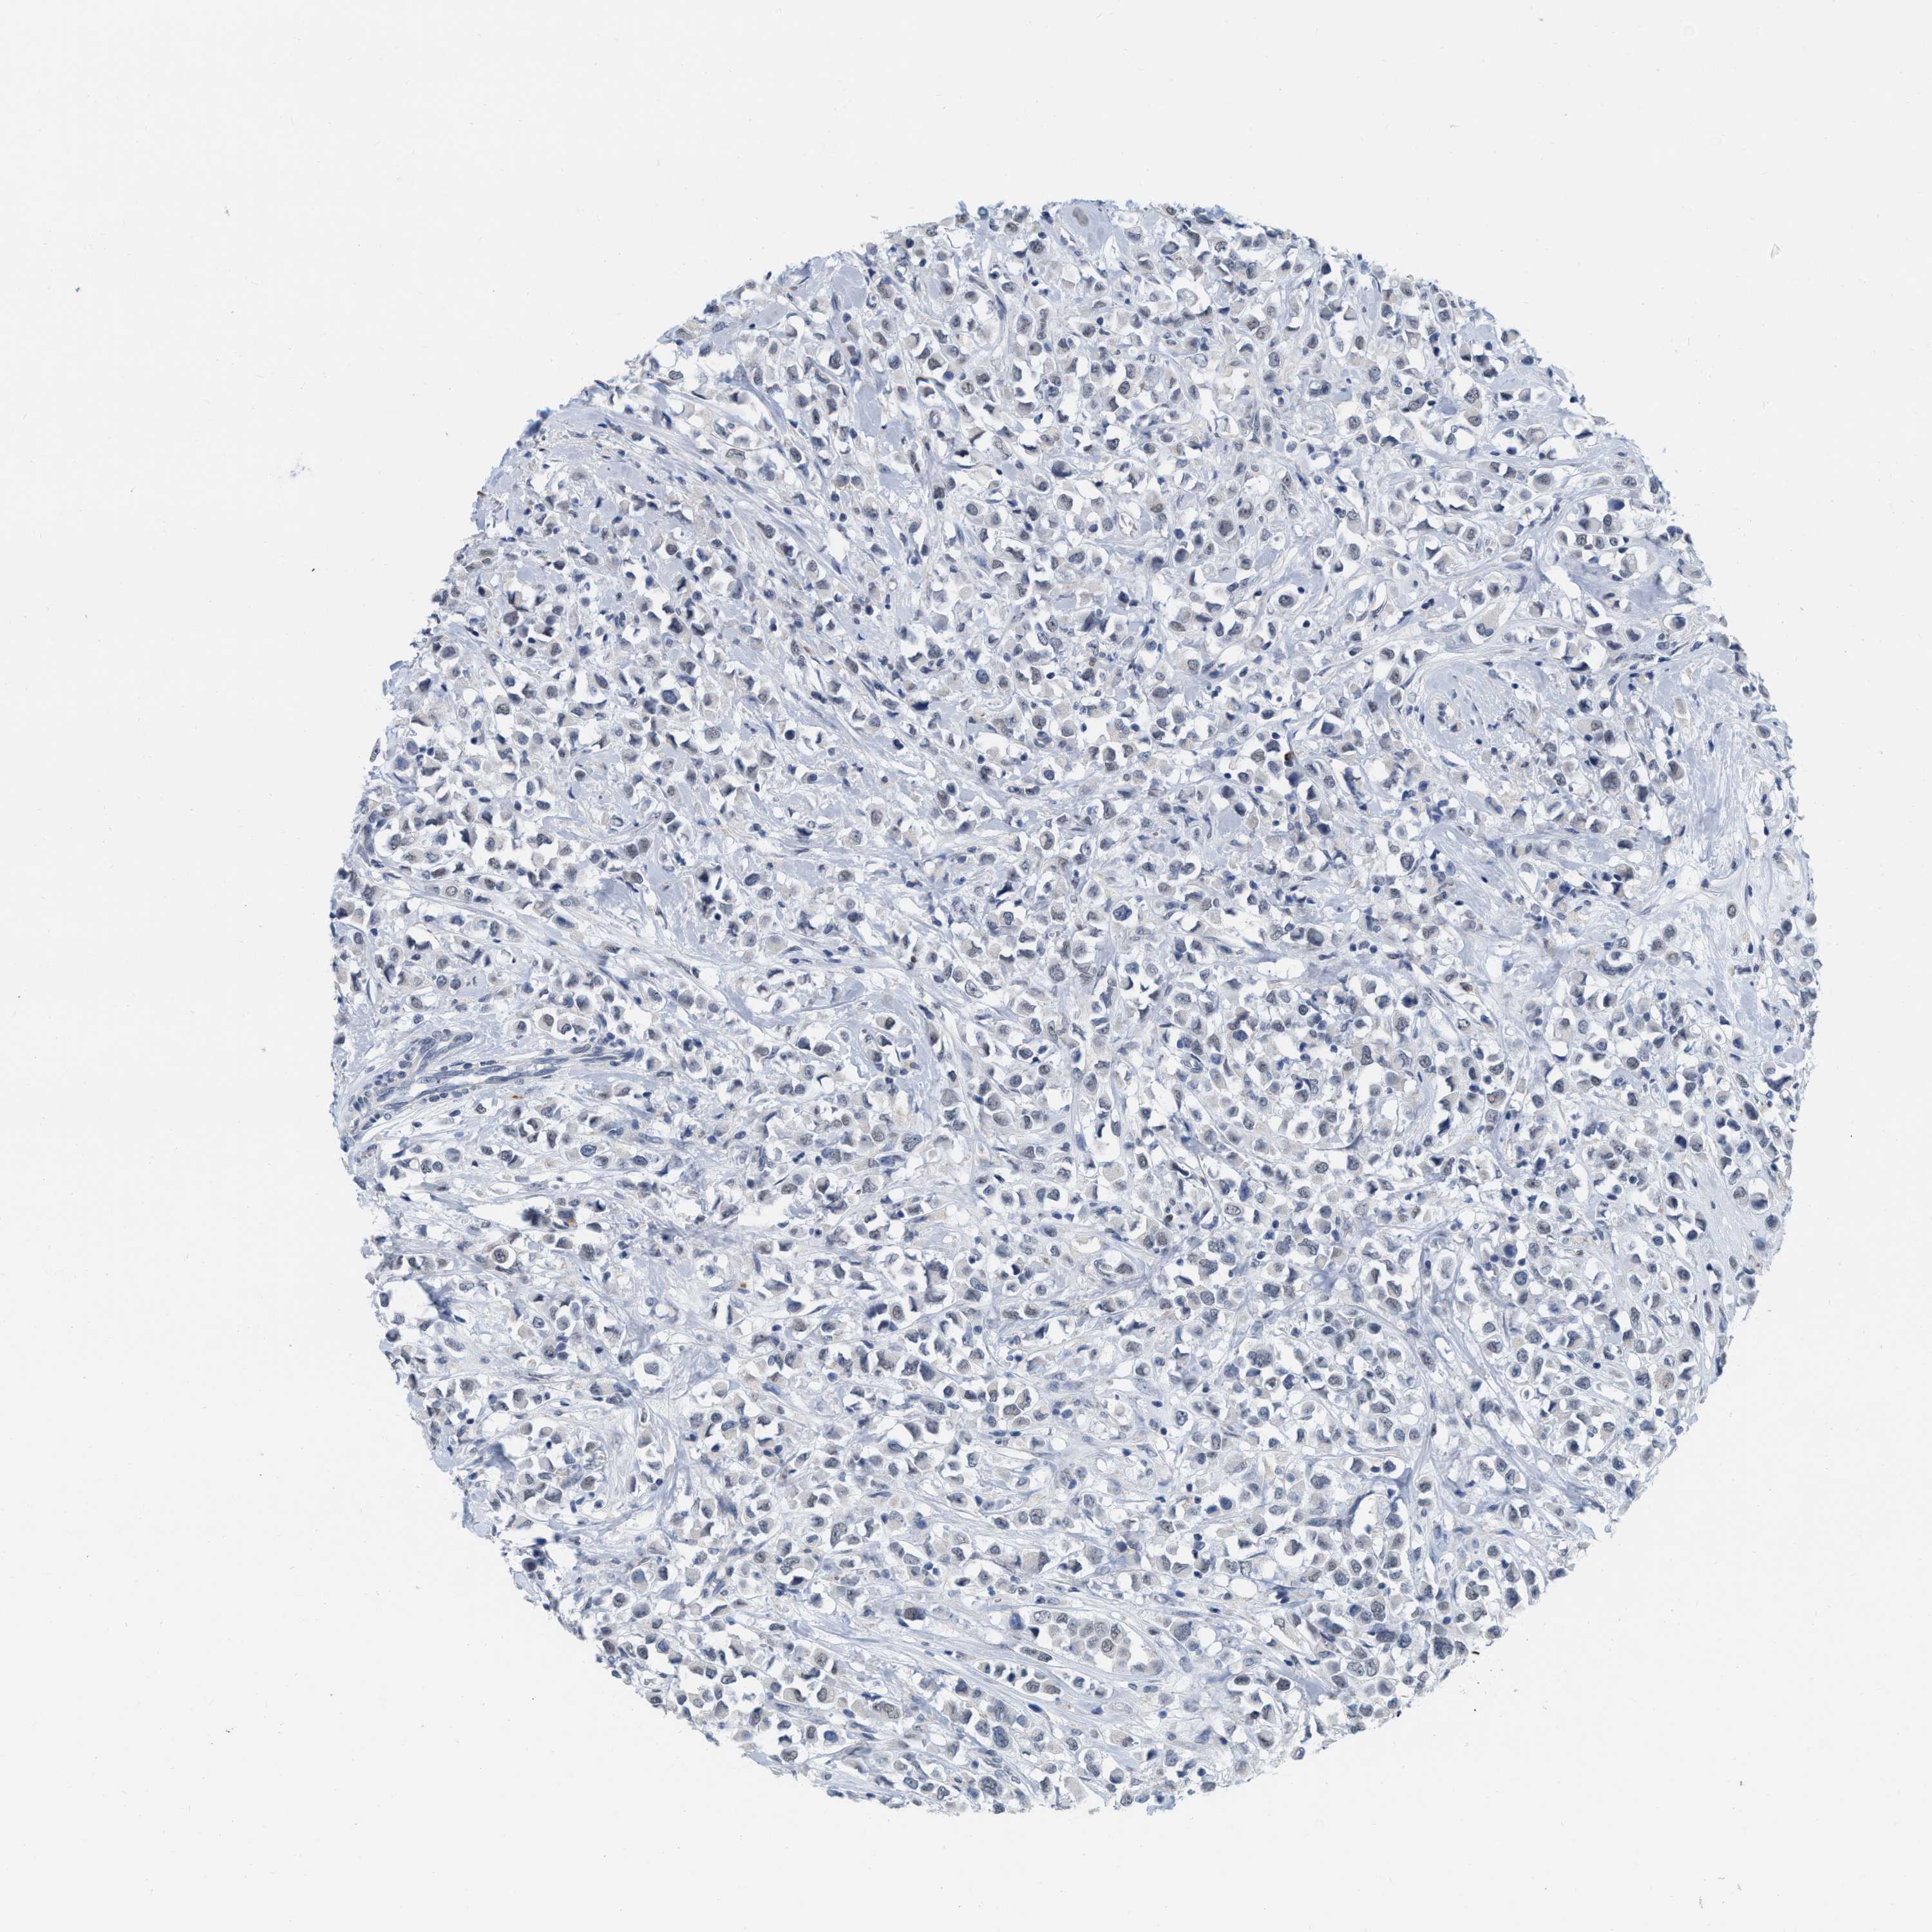

BRCA TCGA BRCA VALIDATION PROTEIN EXPRESSION